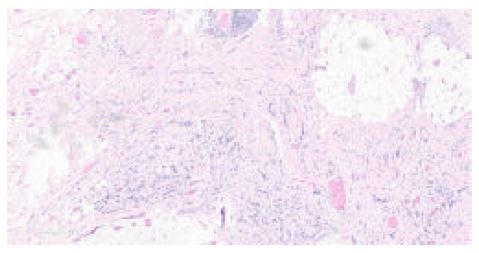

In September 2022, a CT scan of the thorax, abdomen, and pelvis was performed for re-staging. While no pulmonary disease was detected, the scan revealed four suspicious breast nodules (two on each side), as shown in Figure 4. A biopsy later confirmed these nodules to be metastatic sarcoma, identical to the forearm mass, with pathology slides presented in Figures 5 and 6. Prior to the mastectomy, the patient received six rounds of VIT chemotherapy, which included vincristine, irinotecan, and temozolomide. Subsequently, a bilateral mastectomy with partial excision of the pectoralis major muscle was performed in March 2023. The procedure was successful, and no complications were reported. The patient was subsequently referred to physiotherapy.

Figure 6: A low-power view reveals the breast.